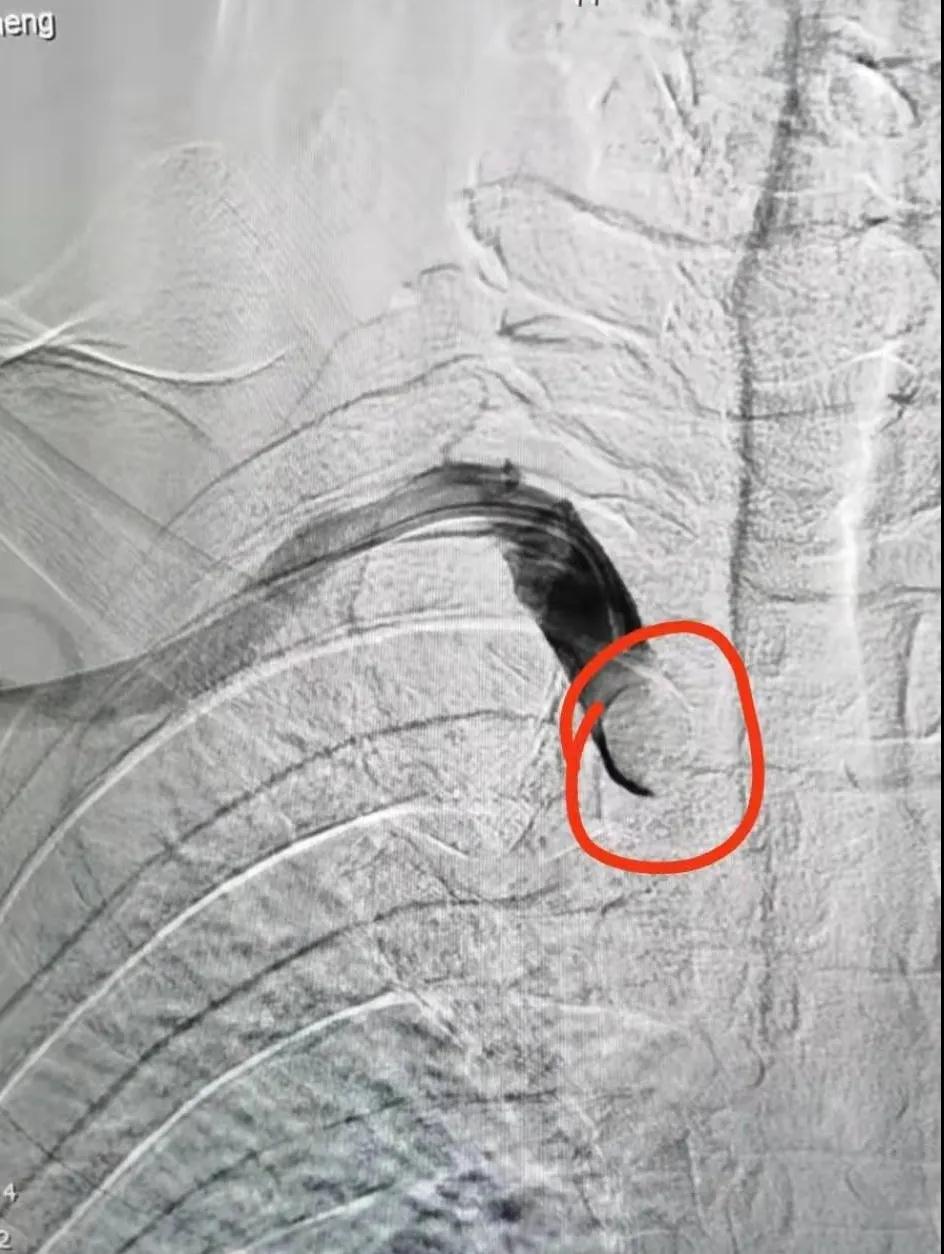

開口處閉塞

造影見大斑快堵塞開口

在征得王先生及家人同意后,魏主任組織介入團隊進行術前討論,依據患者病情擬定了詳細的手術方案,手術由魏主任親自操作,在手術中意想不到的遇到了重重困難:一是斑塊硬開通困難,二是斑塊脫落形成栓塞,三是病灶在夾層,四是支架不能堵塞椎動脈等,給手術帶來很大風險,憑借多年的臨床實踐,終于把血管開通、支架植入。后經造影顯示:右鎖骨下動脈支架置入后恢復前向血流,不再盜血,手術歷時4個小時,整個過程可謂“驚心動魄”。